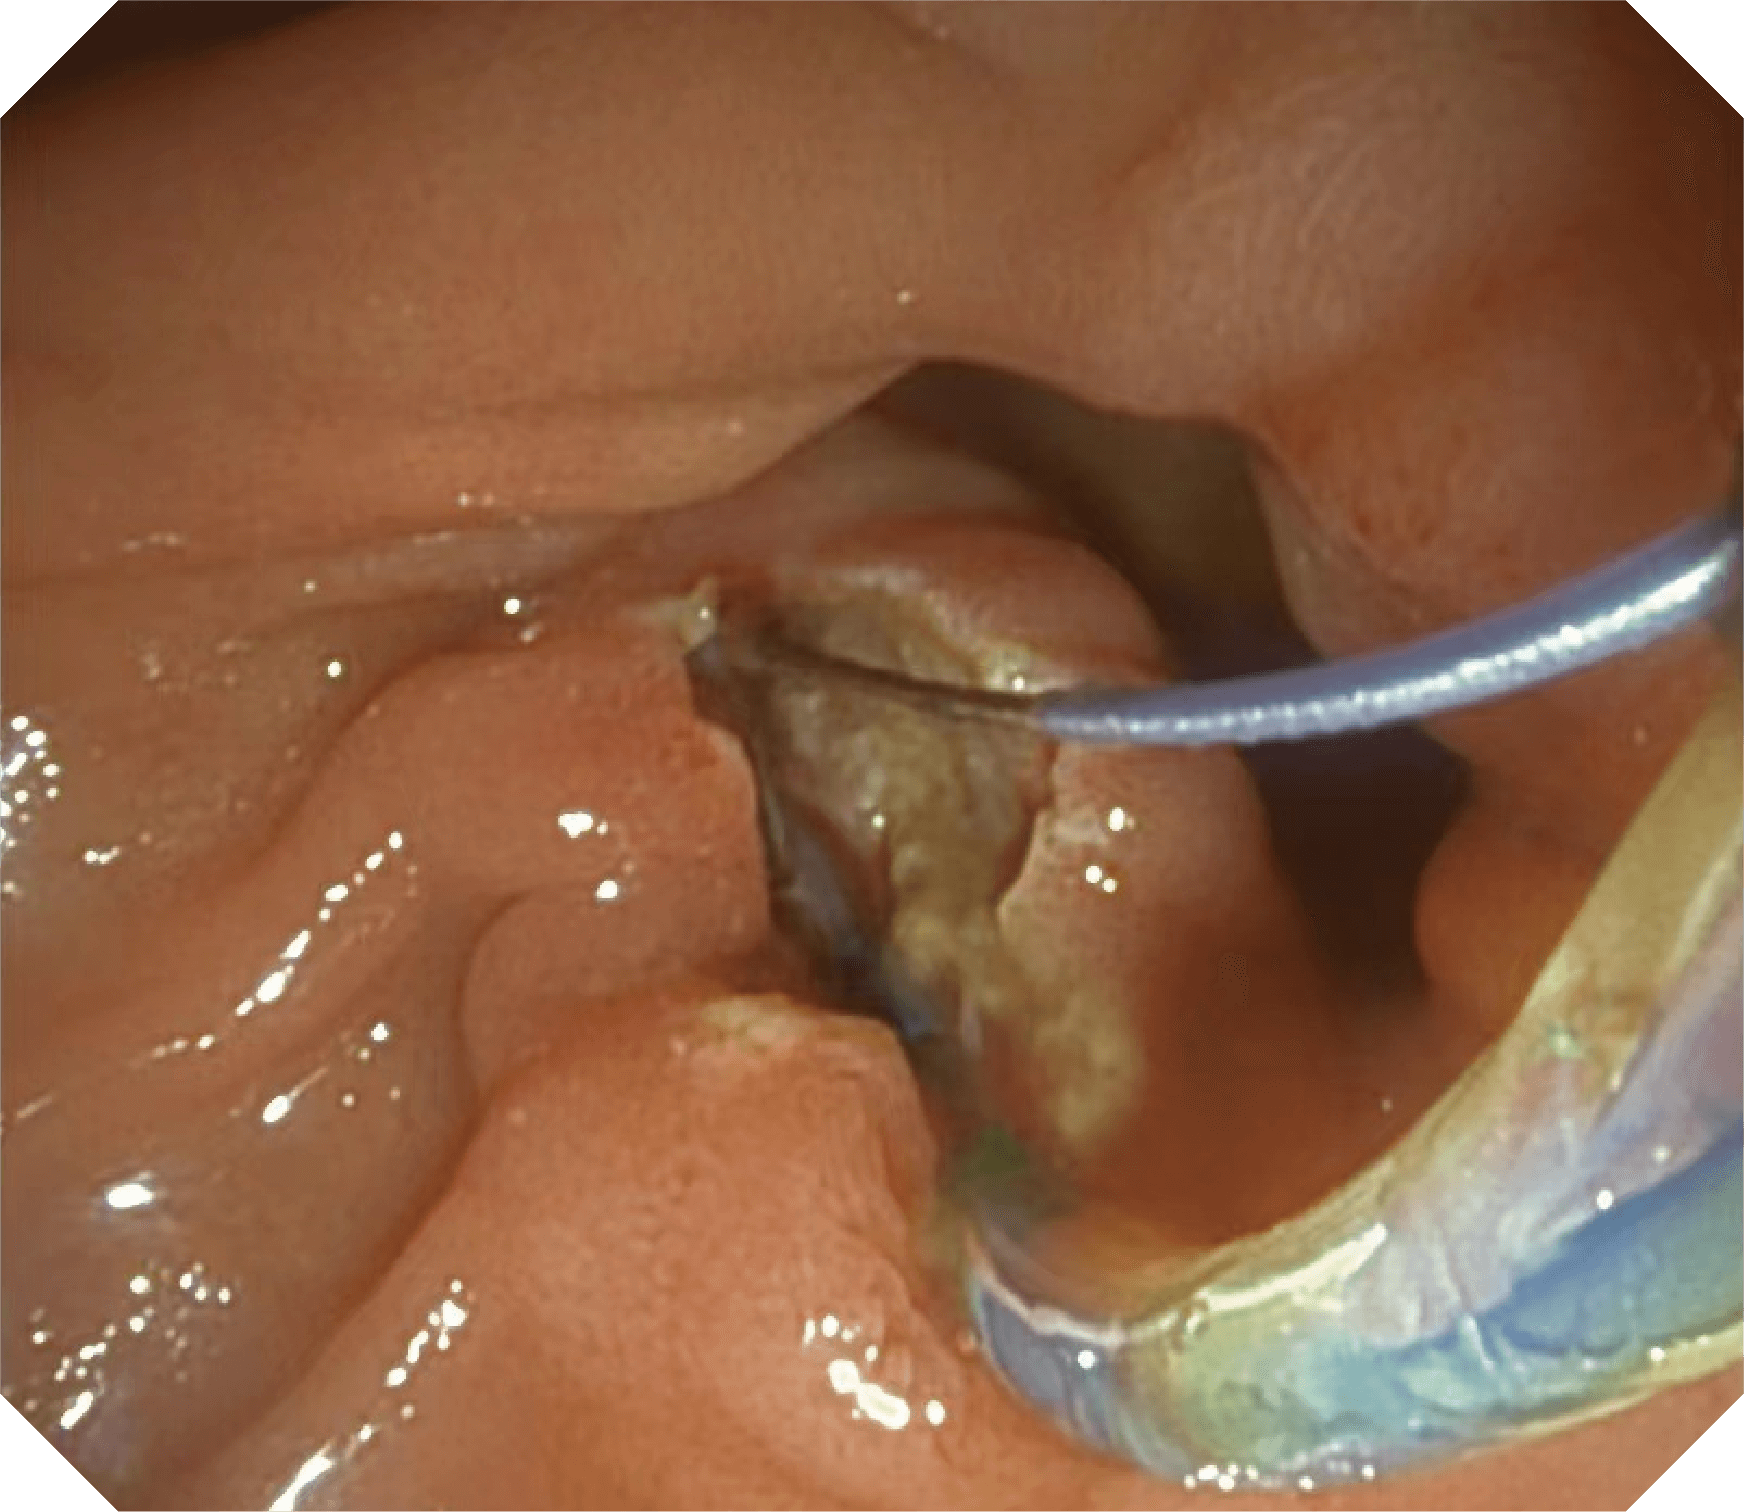

4.2mm大钳道,器械交换更顺畅

V槽设计提升导丝控制

优异的手术器械抬举性